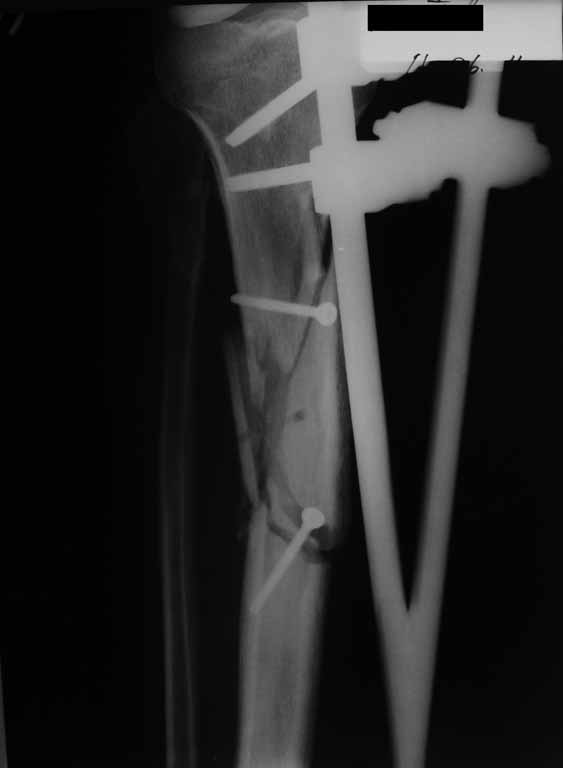

Привожу пример: Пациент с открытой тяжелой ЧМТ.

Диагноз при поступлении: Открытый оскольчатый перелом свода и основания черепа,субдуральная гематома, ушиб головного мозга тяжелой степени. Открытый оскольчатый перелом костей правой голени. Шок 3 Кома 3

При поступлении оперирован : трепанация, ПХО, остеосинтез голени.

Консолидация в аппарате внешней фиксации к 2 месяцам. Аппарат снят через 2,5 месяца.